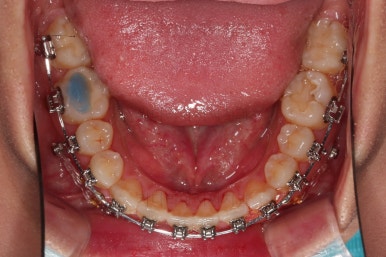

치열의 고른 느낌 좋고요.

덧니, 교합, 중앙선 등 모든게 좋아졌네요.

부산치아교정치과 전후 비교해 보겠습니다.

교합, 맞물림, 중앙선, 덧니, 입매, 앞니위치 및 각도 모든게 잘 마무리 되었습니다.

비발치로 오히려 입이 들어가게(악궁확장이나 치간삭제(공간확보의 목적) 없이도) 할 수 있었던 부산치아교정치과 좋은 치료였습니다.